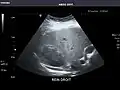

Kidneys: Right and left kidneys measure 11.5 cm and 12 cm in length respectively. No hydronephrosis. Small left lower pole kidney cyst.

Right kidney -